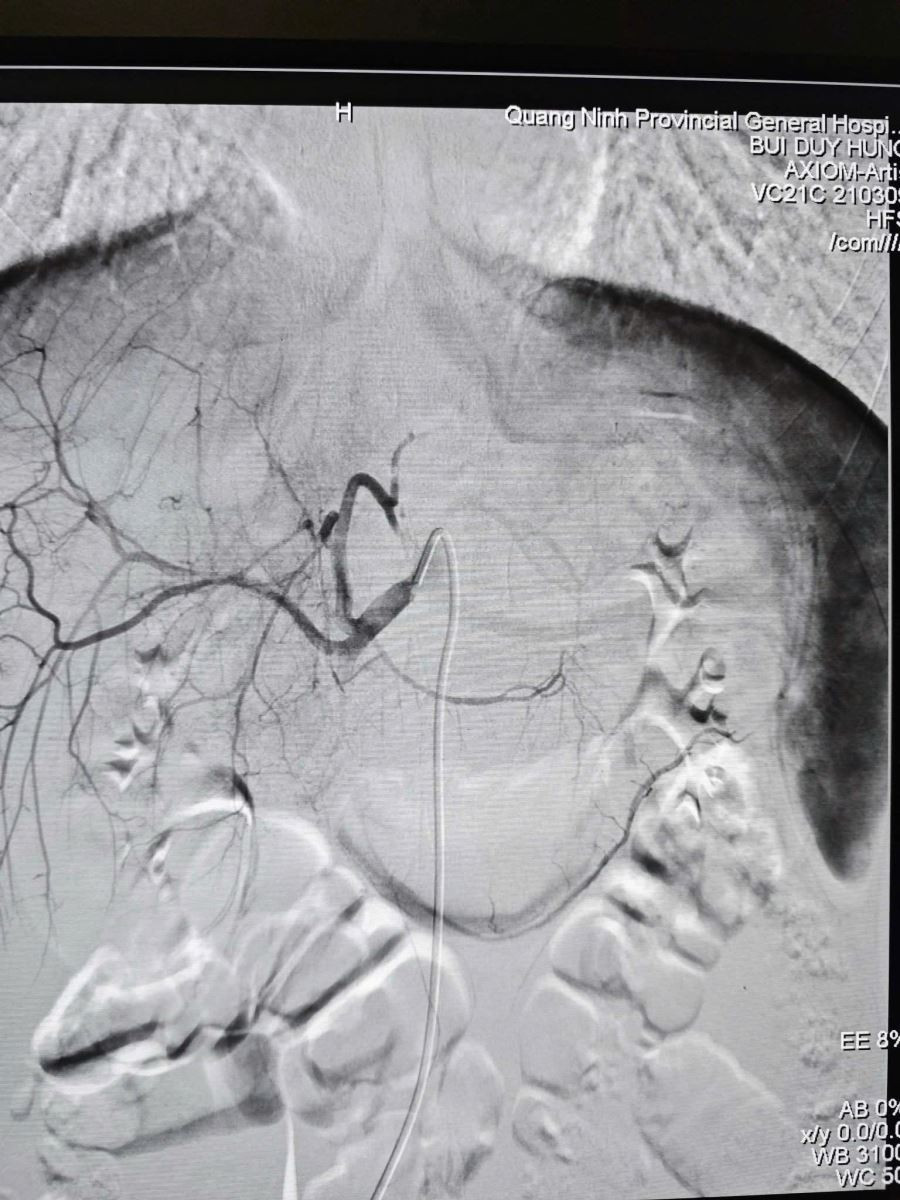

Khi vận chuyển người bệnh về tại cơ sở chính, ê-kíp Can thiệp mạch đã sẵn sàng mọi nguồn lực. Ngay khi tiếp nhận, nhận thấy bệnh nhân có dấu hiệu thiếu máu, các bác sĩ đã chỉ định truyền máu kịp thời trước khi can thiệp. Dưới sự hỗ trợ của hệ thống DSA hiện đại, ê-kíp bác sĩ đã luồn ống thông (Microcatheter) siêu nhỏ 1.9F tiếp cận siêu chọn lọc vị trí nhánh động mạch gan đang chảy máu và nút tắc bằng vật liệu chuyên dụng Spongel.

Hình ảnh sau nút mạch điều trị chấn thương gan, ổ chảy máu đã được nút tắc./Ảnh BV

Sau 60 phút, ca can thiệp thành công tốt đẹp, hình ảnh chụp kiểm tra cho thấy điểm chảy máu đã được cầm hoàn toàn. Huyết động bệnh nhân ổn định và được chuyển hậu phẫu theo dõi với tiên lượng phục hồi. Thành công của ca bệnh khẳng định hiệu quả của mô hình hoạt động đồng bộ, năng lực chẩn đoán tại chỗ nhanh, chính xác ngay từ đầu nhờ CT Scanner và nhân lực chất lượng làm chủ kỹ thuật nút mạch giúp xử trí chấn thương nhẹ nhàng, hiệu quả cao.